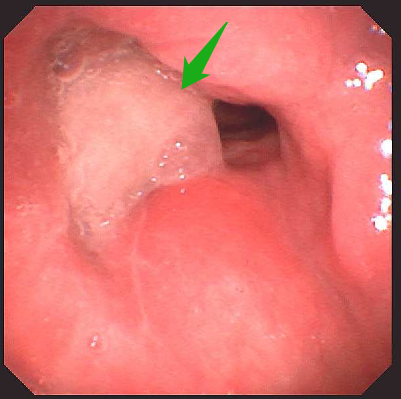

今年 60 岁的张大叔(化名)半年前突然感到声音嘶哑,说话费力。想着自已平日身体硬朗便完全没放在心上,抽烟饮酒也一如既往,直至声音越来越哑、吐词不清,感觉都不是自己在说话,到当地医院检查后,纤维喉镜发现,张大叔的喉腔右侧室带、声带新生物样隆起,表面粘膜不平整,且右侧声带完全固定。

医生考虑喉新生物为恶性肿瘤,已经到了中晚期,建议先活检,再全喉切除。但张大叔平日里喜欢与朋友畅谈,不肯切全喉,家里的亲戚轮番来劝。耳鼻咽喉头颈外科刘蓉蓉主任、姬长友教授接诊后,立刻完善颈部 CT,显示 1. 右侧室带及声带增厚伴软组织结节形成,考虑新生物,建议病理组织学检查 2. 颈部少许小淋巴结。

取右侧声带病变组织活检,证实了喉癌的判断。考虑到喉癌范围极大,右侧声带已经固定,建议张大叔全喉切除。但其仍「意志坚定」,坚决不切全喉。刘蓉蓉主任、姬长友教授详细研究,制定了把右喉体及右侧甲状软骨板「连锅端」,保留左侧喉组织的方案,既可以彻底解决问题,又照顾到张大叔关于保留喉功能的顾虑。